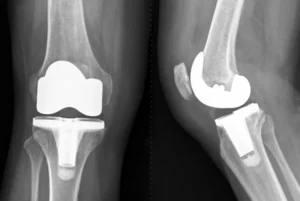

Protheses, also known as a new joint, are made from plastic, metal or both. The prosthesis can be cemented or left uncemented. A prosthesis that is not cemented is made so that bones can grow into it.

When x-rays or other tests reveal joint damage, total knee replacement may be the best option. This is when persistent, moderate-to-severe pain doesn’t improve with nonsurgical treatment and when their knee joint has a limited range of motion that affects their quality life.